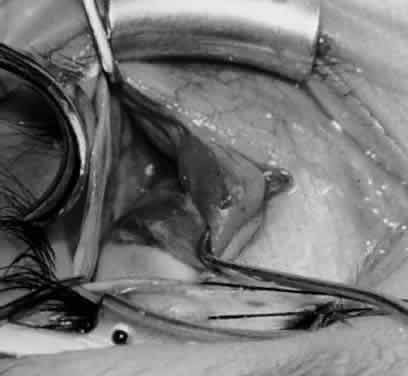

Fig. 24. The eyelid speculum is removed and a Desmarres lid retractor is placed inferiorly. The inferior oblique muscle is drawn superiorly and nasally. The fusiform expansion of the inferior oblique muscle is evident on the posterior border, where the nerve to the inferior oblique muscle and artery and vein enter the inferior oblique muscle. The Stevens muscle hook is used to hook the neurovascular bundle.

Fig. 25. The hook is advanced further for identification of the neurovascular bundle on the inferior oblique muscle.

Fig. 26. Cautery is applied to sever the neurovascular bundle, and a sponge is used to protect the sclera and lids from cautery.

Fig. 27. As the neurovascular bundle is severed completely, the inferior oblique muscle will be released of the normal tension provided by the neurovascular bundle on the posterior border of the inferior oblique muscle.

Fig. 28. The inferior oblique muscle is drawn further into the operative field, and a 3-0 Vicryl suture ligature is applied about the belly of the muscle.

Fig. 29. Cautery is used to sever the inferior oblique muscle and to provide hemostasis.